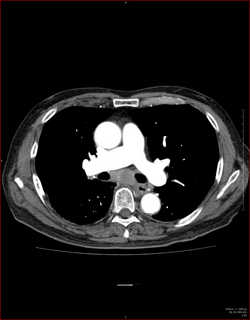

CTで見ると…

気管狭窄ですね。こういう所見もレントゲンで捉えることができるのです。